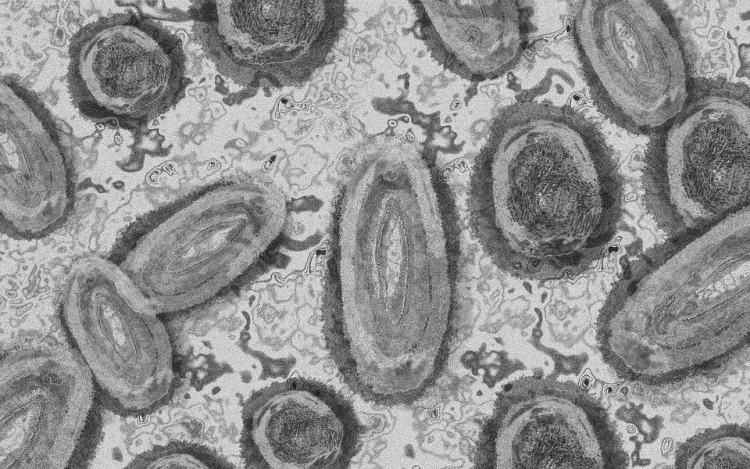

Meghaladta a 13 ezret a majomhimlő-fertőzöttek száma az Egyesült Államokban, a legtöbb esetet Kaliforniában és New York államban regisztrálták.

Az amerikai járványügyi és betegségmegelőzési központ (CDC) szerdán közölt friss tanulmánya szerint a járvány ugyan elsősorban szexuális érintkezés útján terjed, de a fertőzöttek egy része tömegrendezvényeken kapta meg a vírust. A hivatal arra hívja fel a figyelmet, hogy a majomhimlővel bárki megfertőződhet, ha másokkal közeli testi kapcsolatba kerül, akár bőrfelületek érintkezése révén.

A legutóbbi adatok szerint 13 500 fölött van az igazolt fertőzöttek száma, az esetek csaknem felét Kalifornia, New York és Florida államokban regisztrálták.